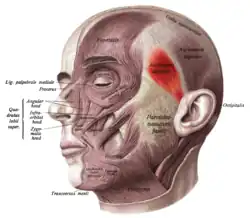

Face and neck muscles. Anterior auricular muscle shown in red. | |